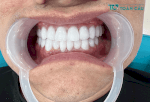

Giá Dán Răng Sứ: Bảng Giá 2024

Bảng Giá Răng Sứ Zirconia Mới Nhất 2023

Bảng Giá Bọc Răng Sứ Ở Hải Dương

Bọc Răng Sứ Giá Bao Nhiêu? Bảng Giá Bọc Sứ Tại Nha Khoa Toàn Cầu